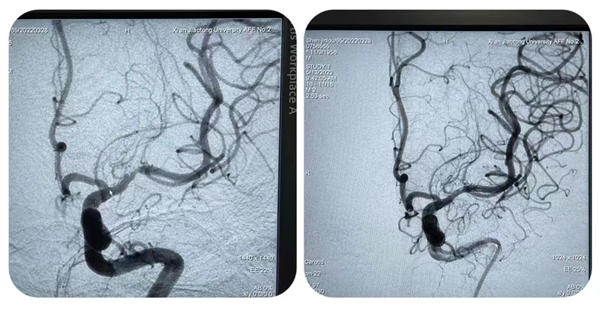

首先,张桂莲主任团队为一例保守药物治疗效果欠佳、反复发作脑梗死、慕名前来我院的患者,实施了左侧大脑中动脉支架植入术,并对患者麻醉苏醒后状态进行了直播。颅内症状性动脉狭窄因颅内血管腔大壁薄、操作复杂、技术要求高、手术风险大等特点,属于神经介入高难度手术,是优秀介入团队的标志。张茹副主任从手术指征、手术准备、手术操作、术后护理等方面进行了详细的剖析和讲解,手术全程操作流畅,术后患者恢复良好,并于术后第二天顺利出院。

图片1_副本.png